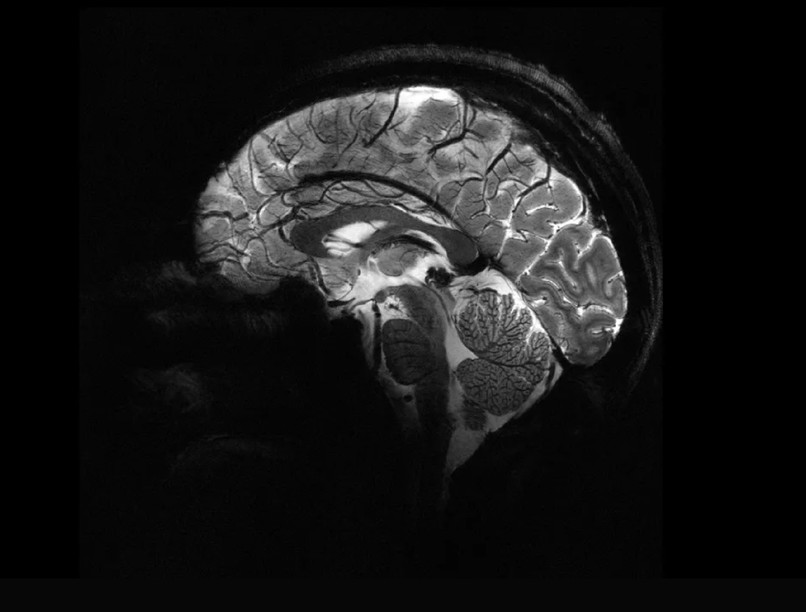

A gép alig négy perc alatt olyan részletes agyképet készített, amelyet eddig több órányi munkával sem.

A francia atomenergia-bizottság (CEA) kutatói beüzemelték a világ legnagyobb erejű MRI-készülékét, hogy demonstrálják annak képességeit. Az eredmény lenyűgöző volt: a gép alig négy perc alatt olyan részletes agyképet készített, amelyet a hagyományos eszközök több órányi munkával sem tudtak volna megvalósítani – számol be az IFLScience.

A mágnesesrezonancia-képalkotó berendezések erős mágneses térrel veszik körbe a vizsgált testrészt. Míg a legtöbb kórházi eszköz 1,5-3 tesla (T) erősségű, a mostani gép 11,7 T-vel dolgozik, ami rendkívül részletes felbontást tesz lehetővé sokkal rövidebb idő alatt. Ez különösen fontos, mivel a betegek csak rövid ideig tudnak mozdulatlanul feküdni. Az új technológia nagy segítséget jelenthet az Alzheimer-kór és a Parkinson-kór kutatásában, mivel részletesebb információkat szolgáltathat az agy elváltozásairól, ami hatékonyabb terápiák kifejlesztését teszi lehetővé.